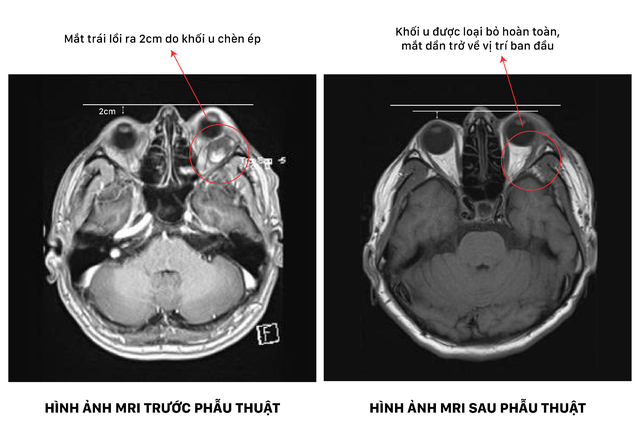

Những hình ảnh chụp MRI sau đó đã hé lộ nguyên nhân thực sự phía sau tình trạng kéo dài suốt nhiều năm. Ẩn sâu sau nhãn cầu bên trái là một khối u kích thước khoảng 2.2 x 2.2 x 4 cm – "khối u giấu mặt" âm thầm phát triển mà trước đó anh không hề hay biết. Chính khối u này đã liên tục đẩy nhãn cầu ra phía trước, đồng thời chèn ép dây thần kinh thị giác, khiến thị lực của anh suy giảm dần theo thời gian.

Theo ThS-BS.CKII Đỗ Anh Vũ, bác sĩ khoa Ngoại thần kinh - Cột sống, u hốc mắt không phải là tình trạng hiếm gặp nhưng dễ bị bỏ qua do tiến triển âm thầm. Đối với trường hợp anh T. khối u nằm tại vị trí khá phức tạp ngay vùng đỉnh bên hốc mắt, nơi tập trung rất nhiều dây thần kinh thị giác và hệ thống cơ vận nhãn ngoài điều khiển mọi cử động của mắt. Khối u không chỉ đẩy nhãn cầu ra phía trước gây mất thẩm mỹ mà còn đang tạo áp lực trực tiếp lên dây thần kinh thị. Nếu không thực hiện phẫu thuật loại bỏ khối u kịp thời, người bệnh đứng trước nguy cơ suy giảm thị lực vĩnh viễn.

Hình ảnh MRI trước và sau khi mổ của người bệnh

Sau hơn 4 giờ căng thẳng, khối u dài khoảng 4cm đã được lấy ra nguyên vẹn. Kết quả giải phẫu bệnh xác định đây là u mạch máu dạng hang lành tính, một thông tin giúp anh T. và gia đình như trút bỏ gánh nặng tâm lý đã đè nặng suốt nhiều năm.

Những thay đổi sau phẫu thuật đến một cách rõ ràng. Nhãn cầu mắt trái dần trở về vị trí tự nhiên, cảm giác nặng nề trong hốc mắt biến mất. Đặc biệt, thị lực hai mắt sau mổ ổn định (10/10), không ghi nhận suy giảm, giúp anh T. yên tâm trong sinh hoạt hằng ngày. Chỉ sau một tuần chăm sóc hậu phẫu, anh T. đã có thể xuất viện trong niềm vui và sự nhẹ nhõm của cả gia đình – khép lại hành trình kéo dài nhiều năm bằng một kết quả trọn vẹn.